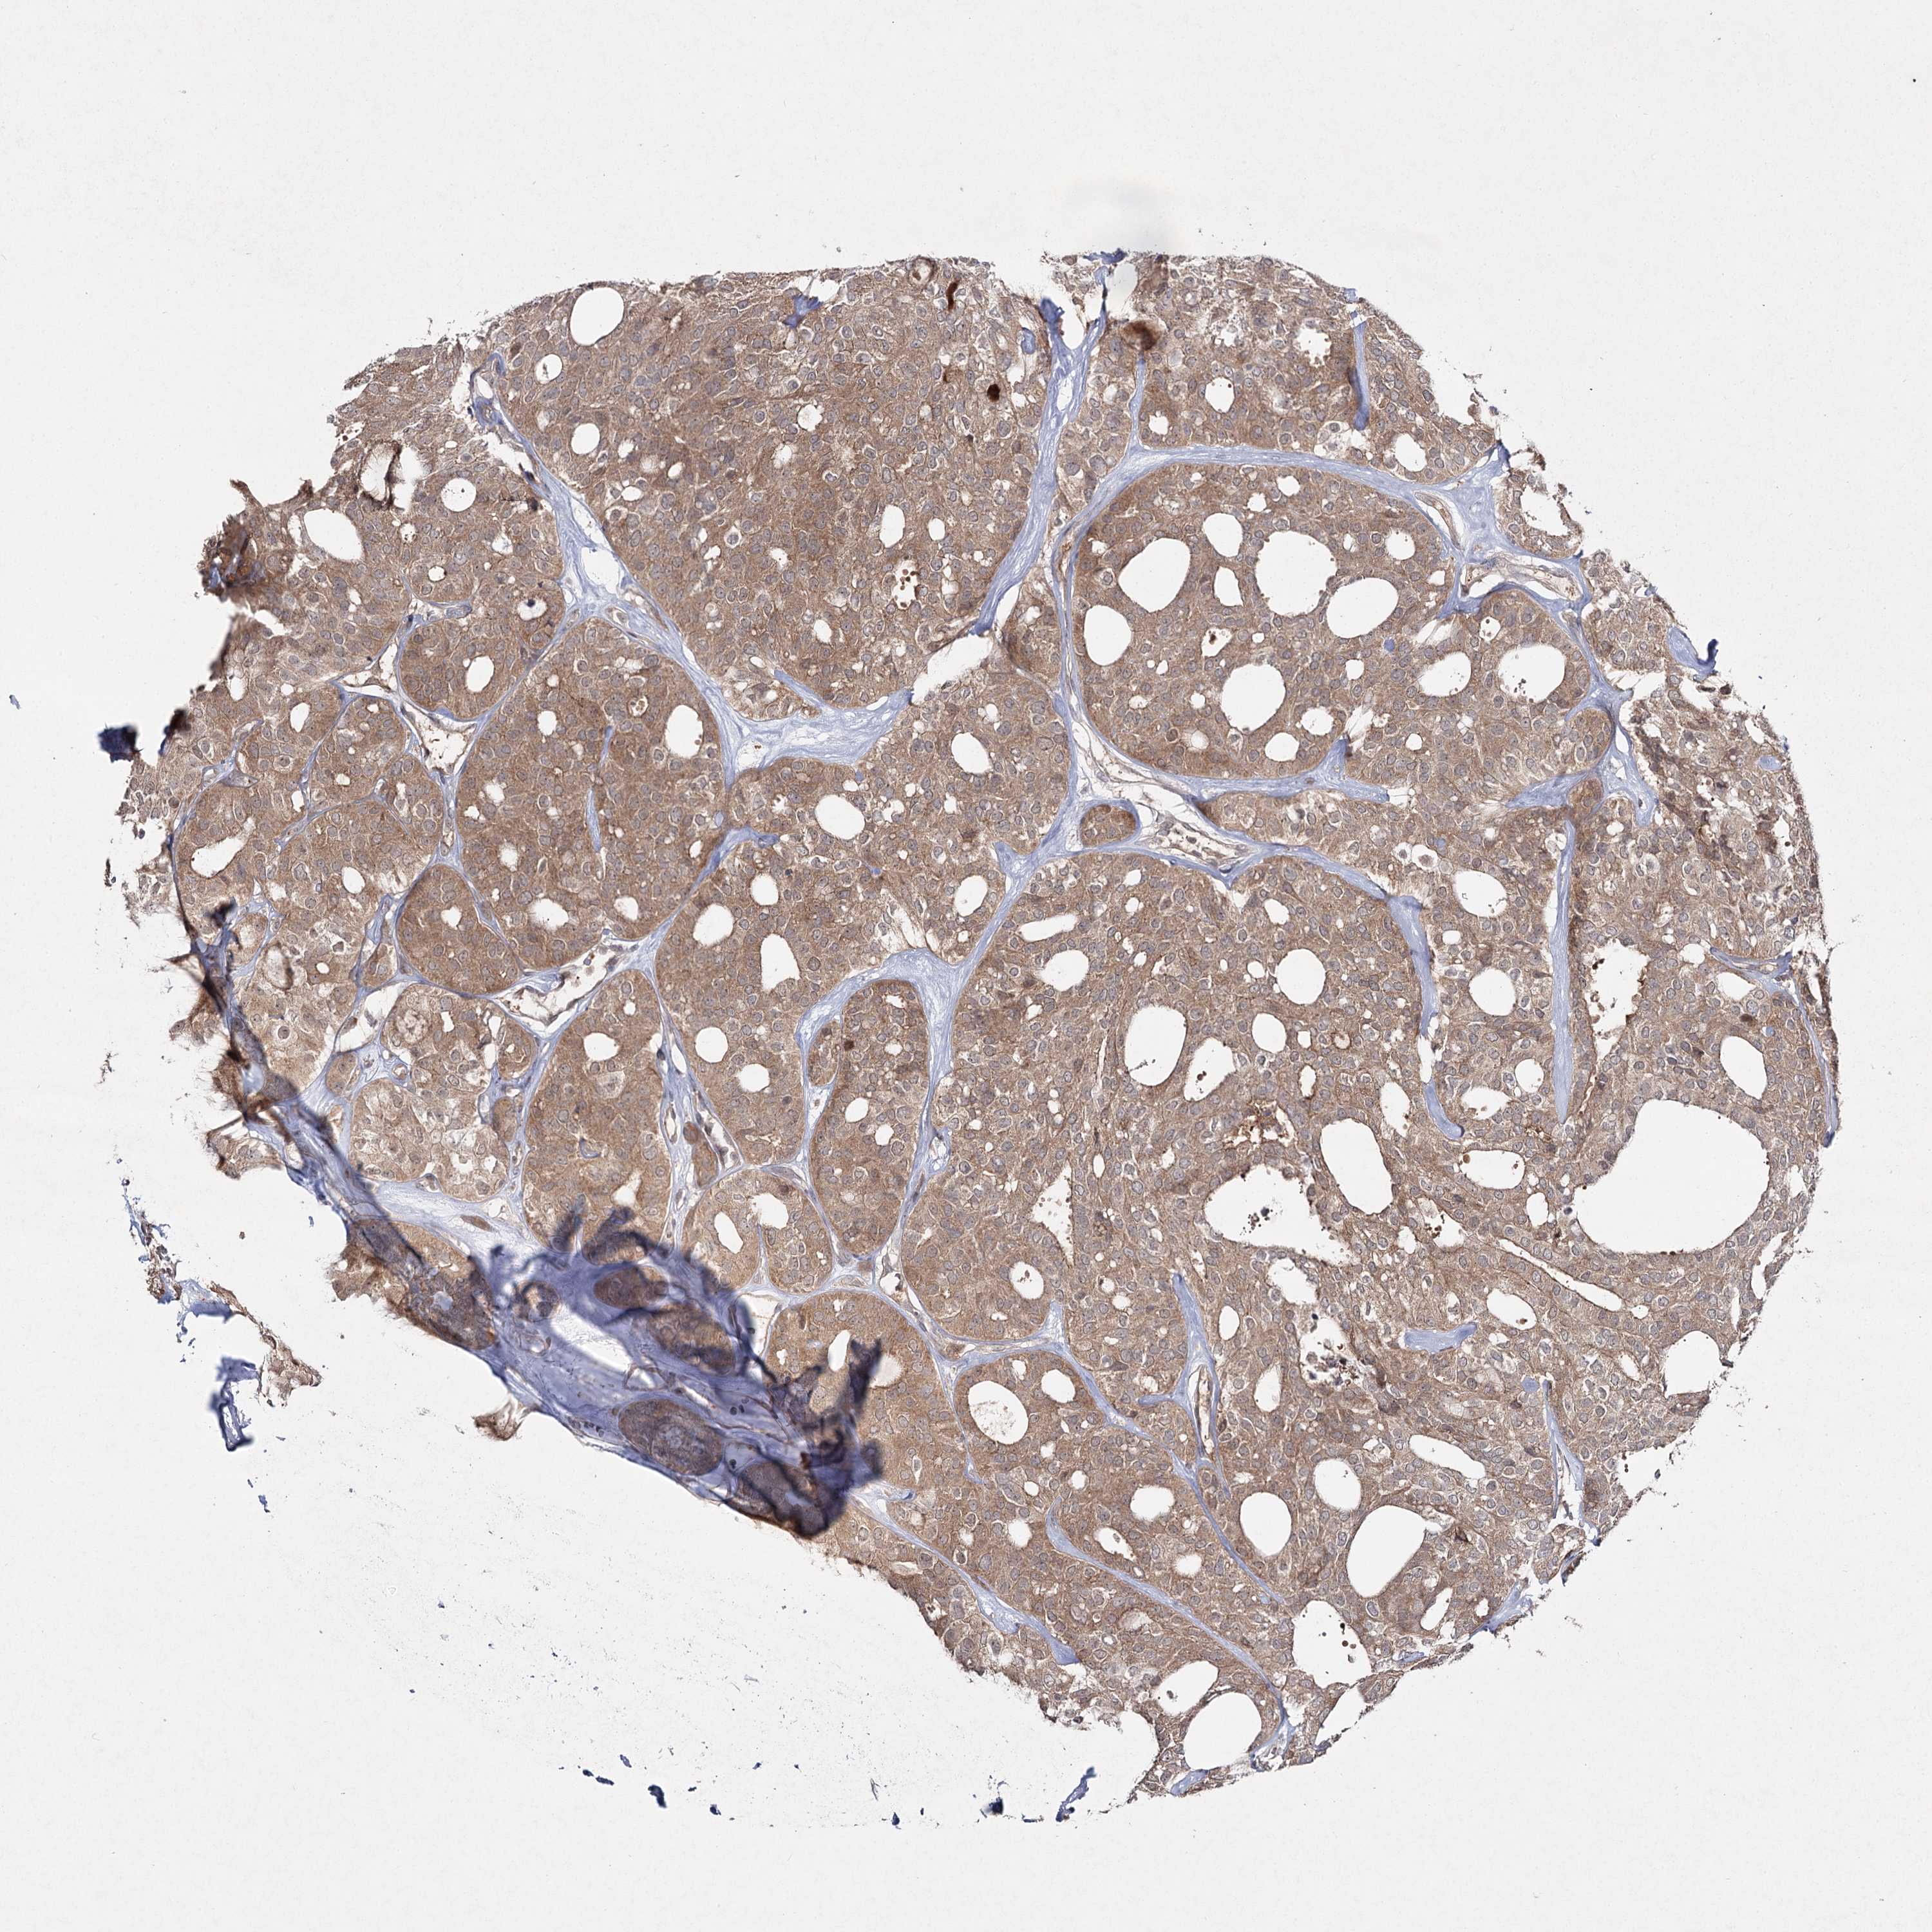

THYROID CANCER - Protein expressioni

A mouse-over function shows sample information and annotation data. Click on an image to view it in a full screen mode. Samples can be filtered based on level of antibody staining by selecting one or several of the following categories: high, medium, low and not detected. The assay and annotation is described here.

Note that samples used for immunohistochemistry by the Human Protein Atlas do not correspond to samples in the TCGA dataset.

Antibody stainingi

Antibody staining in the annotated cell types in the current human tissue is reported as not detected, low, medium, or high, based on conventional immunohistochemistry profiling in selected tissues. This score is based on the combination of the staining intensity and fraction of stained cells.

Each image is clickable and will lead to virtual microscopy that enables deeper exploration of all samples and also displays staining intensity scores, fraction scores and subcellular localization as well as patient and tissue information for each sample.

Antibody HPA038084

Staining

High

Medium

Low

Not detected

Intensity

Strong

Moderate

Weak

Negative

Quantity

>75%

75%-25%

<25%

None

Location

Nuclear

Cytoplasmic/membranous

Cytoplasmic/membranous,nuclear

Papillary adenocarcinoma, NOS

Follicular adenoma carcinoma, NOS